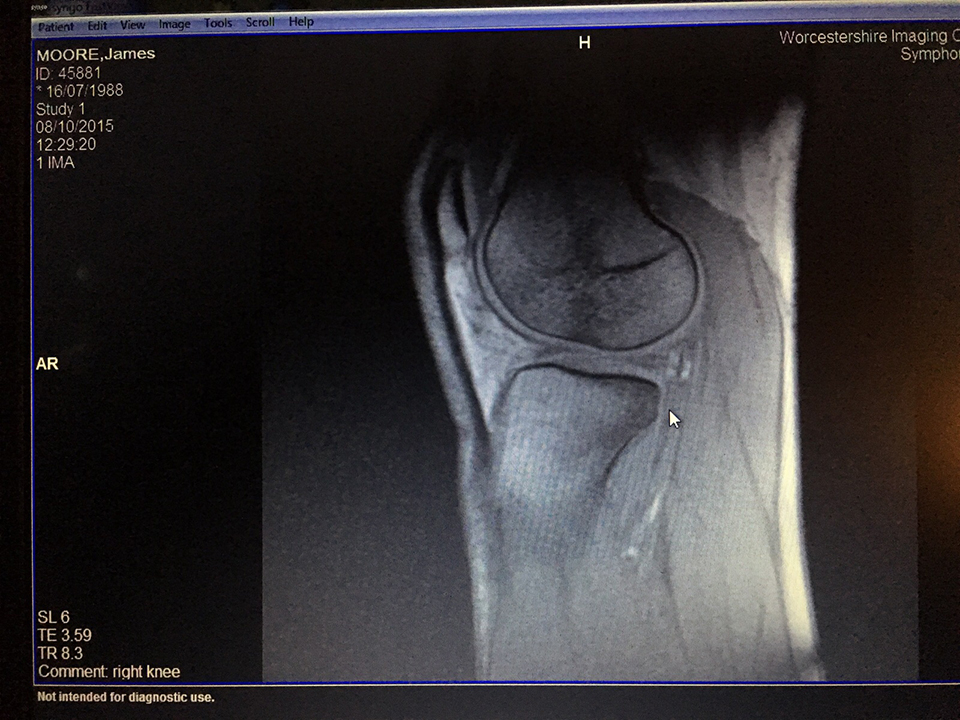

Moore has torn his ACL in his right knee and is likely to miss the remainder of the season.

Cromwell fractures shinbone, and ruptures ACL and MCL in his left knee.

Chaps legend completes knee operation

Vicious rumours circulate about the true nature of our founders' injury...